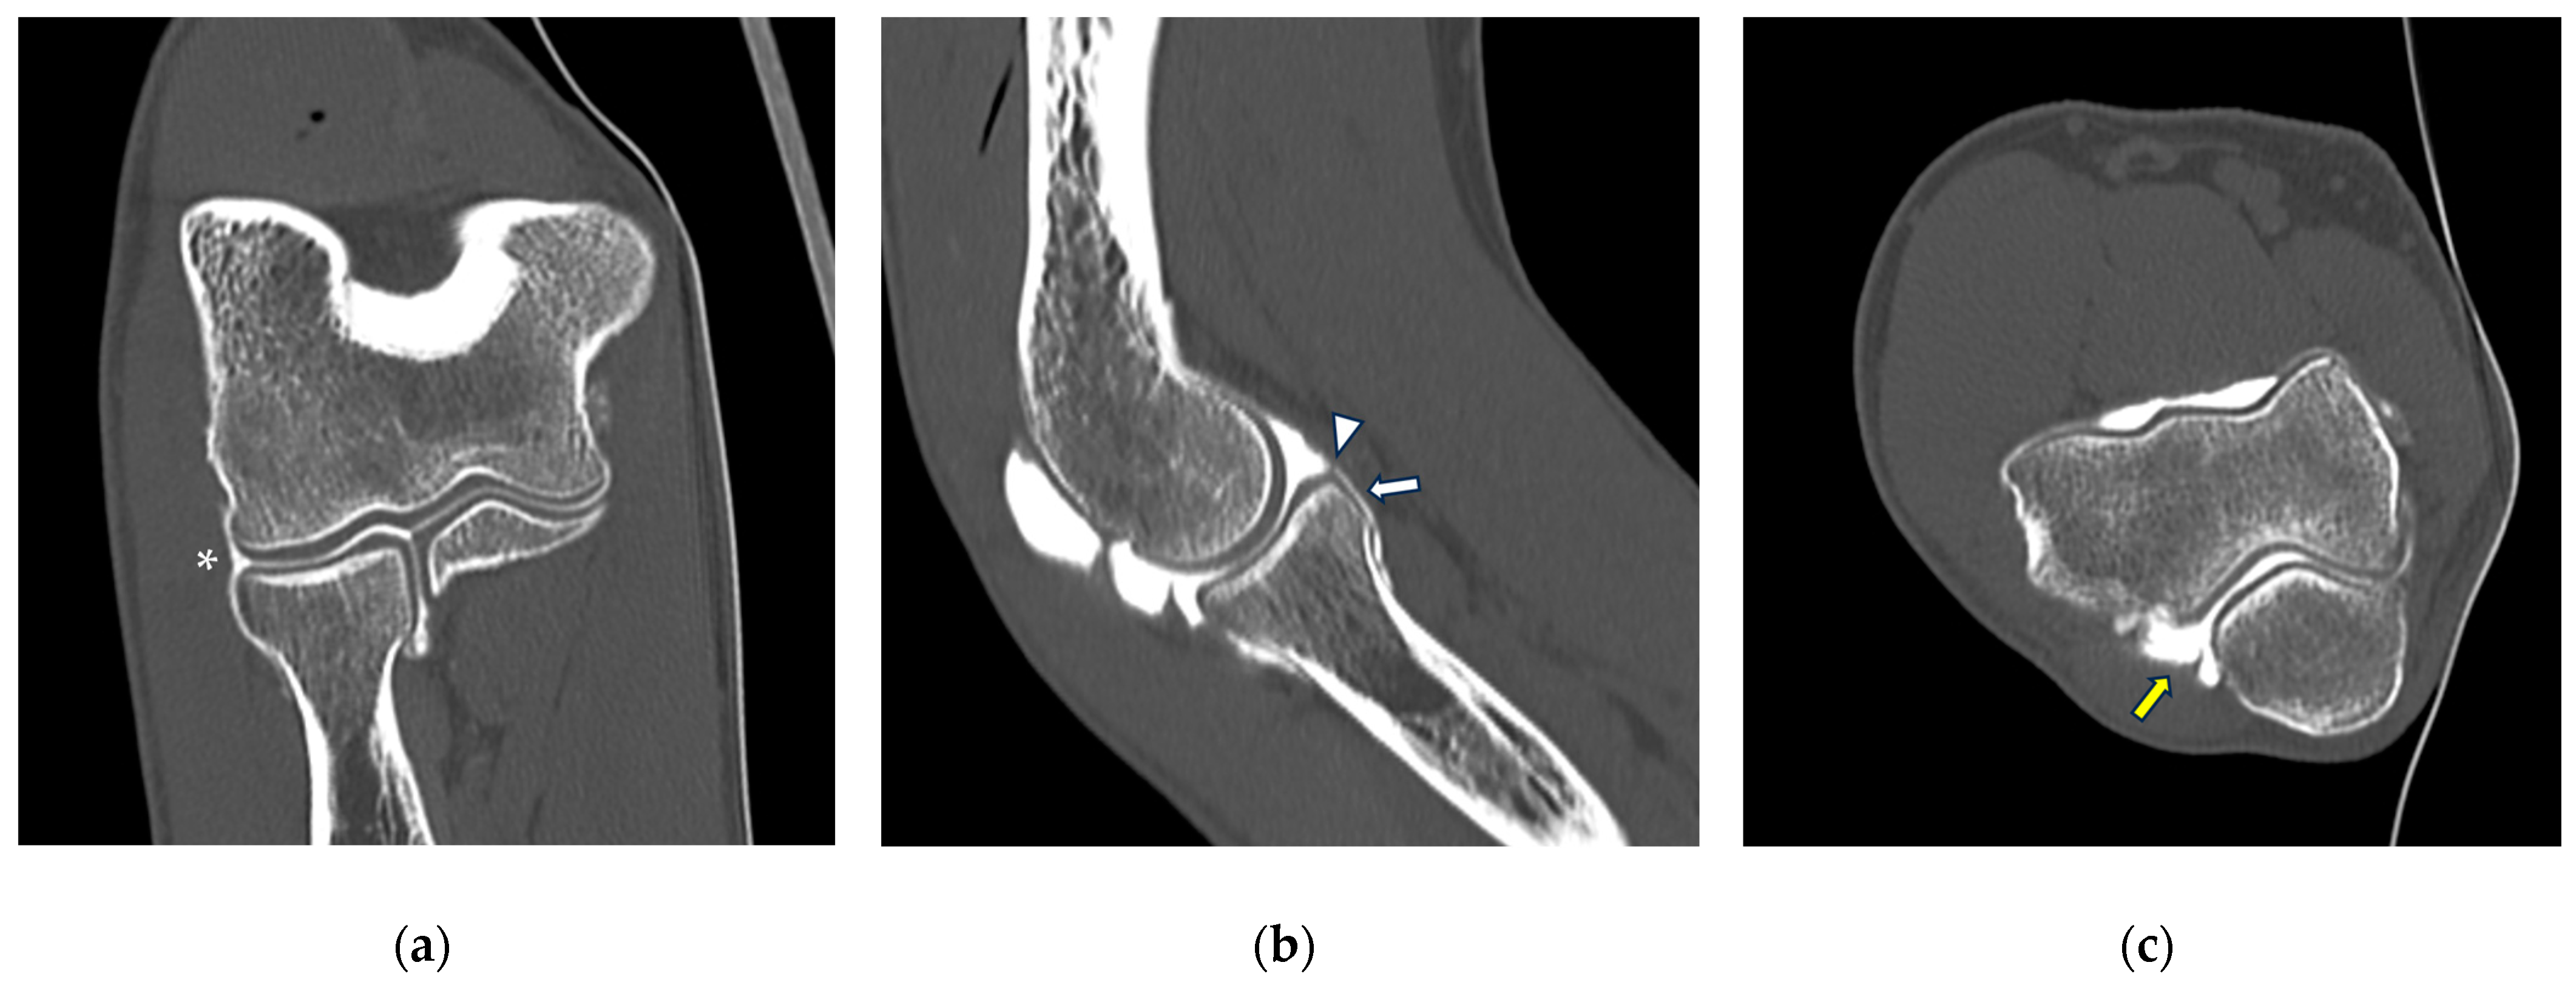

Figure 2.

CT arthrography of the elbow—normal anatomy. (a) Coronal image shows a regular chondral lining of the radio-humeral, ulno-humeral, and radio-ulnar joints, with no evidence of focal chondral lesions. The articular capsule is not pathologically distended and there is only a physiological amount of contrast in the lateral radio-humeral recess (asterisk), indicating the presence of an intact radial collateral ligament; (b) sagittal image shows an undisplaced annular ligament (white arrowhead), as well as a regular chondral lining of the radial head side and a physiological sliver of contrast in the annular recess (white arrow); (c) axial image shows a physiological amount of fluid in the posterior recess of the elbow (yellow arrow), with no evidence of loose bodies, as well as regular chondral lining of the humerus and olecranon.